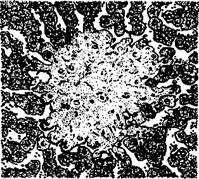

Сальмонеллезная гранулема в печени теленка

Гранулемы (паратифозные узелки) имеют вид очажков размножающихся ретикулоэндотелиальных элементов, расположенных по ходу капилляров. Клетки гранулем со светлыми крупными ядрами обладают способностью к фагоцитозу. Кроме печени и селезенки паратифозные узелки отмечают также в почках, лимфатических узлах, костном мозге. В печени и реже в других органах можно наблюдать образование очаговых эндофлебитов, но они не патогномоничны для сальмонеллеза.